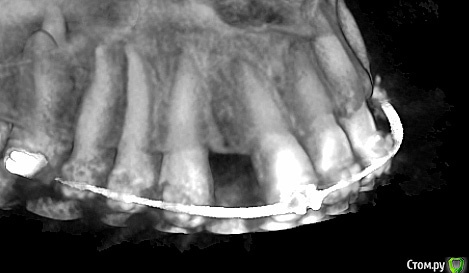

Romanson Опубликовано 13 ноября, 2018 Поделиться Опубликовано 13 ноября, 2018 Здравствуйте.Интересует мнение коллег.Брекеты сняли более года назад.Импланты стоят более года.Как обыграть фронт во втором сегменте? Ссылка на комментарий

Romanson Опубликовано 13 ноября, 2018 Автор Поделиться Опубликовано 13 ноября, 2018 Кроме как превратить клык в двойку и сделать мост 2.2 - 2.4 с клыком вариантов не вижу. Но какой прогноз у такой конструкции?Может кто-нибудь знает другие способы? Ссылка на комментарий